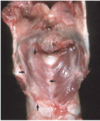

Condition

Glasser’s Disease

Condition

Shipping Fever